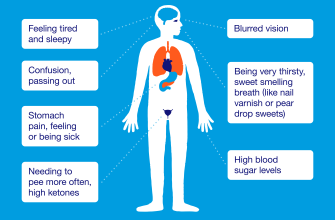

Ketoacidosis is a serious medical condition that occurs